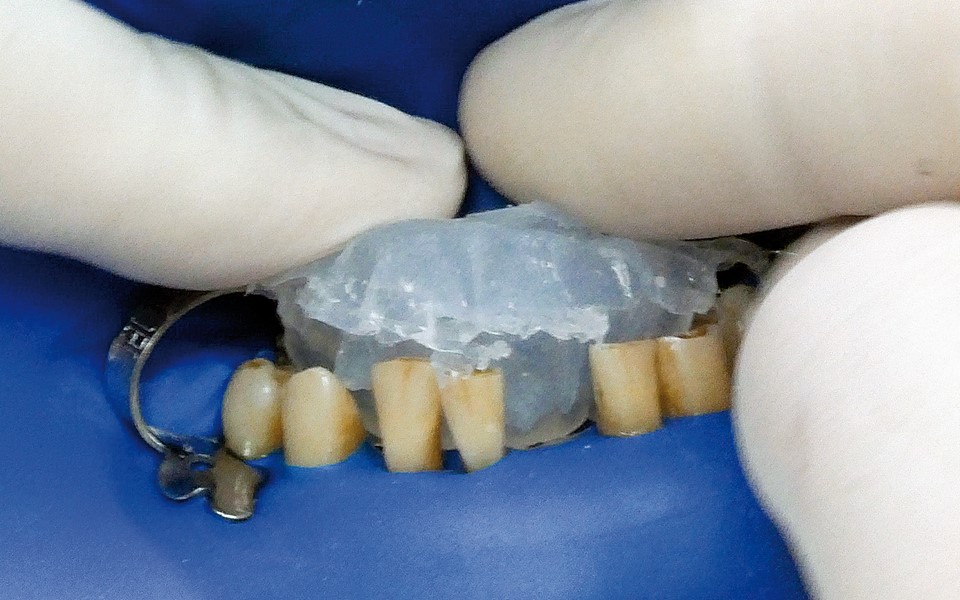

One of the more popular methods of stabilising loose teeth is to splint them. This method, aiding other methods of treatment, is generally used. One of the most modern materials used in dentistry for splinting teeth, is polyamide tape. In the case described the authors show how to simplify the whole procedure and limit the risk of making a mistake, particularly in the situation of total loss of one tooth. This was achieved thanks to the use of an index made out of transparent silicone.

Jedną z popularniejszych metod stabilizacji zębów rozchwianych jest ich szynowanie. Metoda ta, wspierająca inne metody leczenia, jest powszechnie stosowana. Jednym z najnowocześniejszych materiałów wykorzystywanych w stomatologii do szynowania zębów jest taśma poliaramidowa. W opisanym przypadku autorzy pracy przedstawiają sposób uproszczenia całej procedury i ograniczenia ryzyka popełnienia błędu, szczególnie w sytuacji całkowitej utraty zęba. Uzyskano to dzięki zastosowaniu indeksu wykonanego z przezroczystego silikonu.